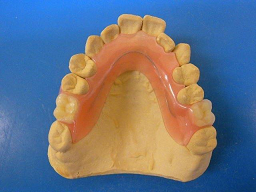

ホワイトコートは、以下のような色調で、自然ではありませんが、多くの方に喜んでもらっていました。これまでは他に方法がなかったので、やむおえません。

このホワイトコートは、3ヶ月くらいで部分的にはがれてきますが、運がよければ1年以上はがれずに維持できています。歯は全く削りません。

術前 ↓

術後

見た目は、やはり グラディアダイレクトには及びません。

今回のグラディアダイレクトは、歯の表面の処理方法や接着方法がホワイトコートよりも優れているので、数年は問題なく維持できると思っています。

おそらくこれからは、見た目の自然さから、ホワイトコートを選ぶ患者さんは減り、グラディアダイレクトに変わっていくと思います。